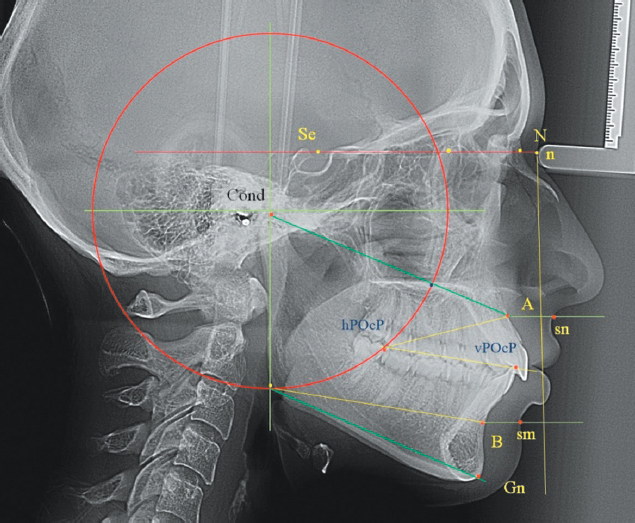

При анализе телерентгенограмм 1-й группы было выявлено, что линия суставного круга, вне зависимости от типологических вариантов роста челюстей (нейтральным, горизонтальным и вертикальным), проходила через дистальную окклюзионную точку второго моляра и через точку, на линии Cond-А, которая находилась от суставной точки на 2/3 величины указанной линии.

Таким образом, выявленная закономерность позволила использовать данный ориентир в качестве диагностики аномалии положения окклюзионного ориентира молярного отдела зубочелюстных дуг.

После определения положения задней точки окклюзионной линии, оценивали ее диагностическое значение с положением других горизонталей лица. При этом точку нижнего диаметра суставного круга соединяли с подбородочной точкой Gn, которая располагалась на передней нижней части подбородочного симфиза. Линия, выходящая из молярной окклюзионной точки параллельно гнатической горизонтали, пересекала в переднем отделе инфрадентальную точку Id, расположенную в верхнем отделе альвеолярной части нижней челюсти и соответствовала расположению шейки нижнего резца. Данный ориентир позволял определить аномалию положения нижних резцов при вертикальной резцовой дизокклюзии или при глубокой резцовой окклюзии/дизокклюзии (рис. 2).

Рис. 2. Особенности расположения окклюзионно-суставной окружности и диагностических линий при физиологической окклюзии.

Fig. 2. Configuration of the occlusal–condylar circle and diagnostic lines in normal occlusion.

В 1-й группе длина окклюзионной линии соответствовала величине, равной отношению расстояния основания черепа (Se-N) к числу Фибоначчи (1,618). Полученные данные могут выступать в качестве диагностического критерия патологических вариантов протрузии или ретрузии передних зубов. Кроме того, было определено равенство длины межокклюзионного расстояния с длиной верхней апикально-окклюзионной линии.